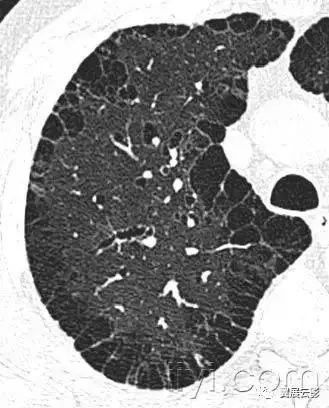

二十、铺路石征:

CT扫描:铺路石征表现为磨玻璃影背景上小叶间隔和小叶内线增厚,呈现不规则的铺路石征。铺路石征常与相对正常肺组织分界清楚,边缘规则。该征象最早报道于肺泡蛋白沉积症,也可见于其他类型同时累及肺间质和肺实质的弥漫性肺疾病,包括脂性肺炎。